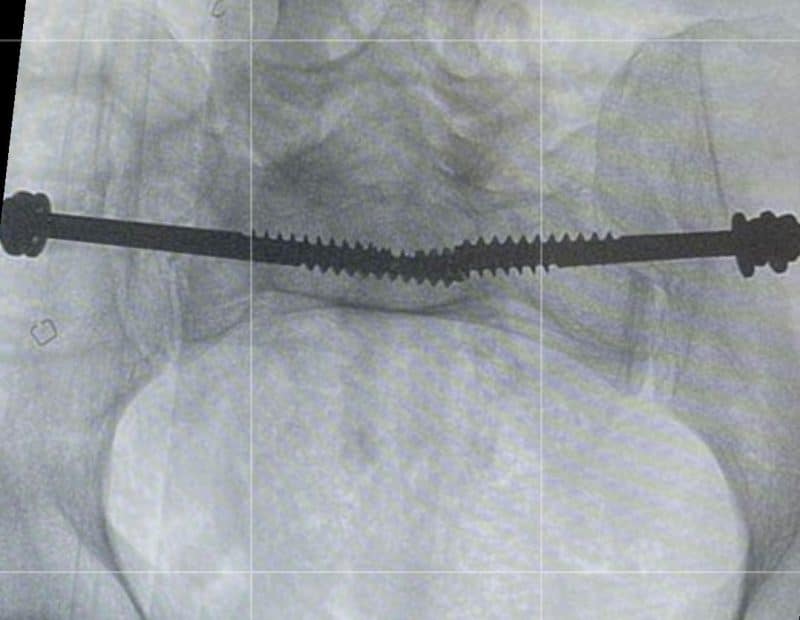

أوضحت “الصحة” أن فريقاً طبياً متخصصاً في قسم العظام في مستشفى الدرعية عضو تجمع الرياض الصحي الثالث تمكن من تثبيت كسر معقد في العظم العجزي في منطقة الحوض للمريض.

وقالت الوزارة إنه تم إرجاع، وتثبيت الخلع في المفصل العجزي الحرقفي لمريض في العقد السادس من العمر عن طريق وضع مسامير طبية باستخدام الأشعة التداخلية.

وأشارت “الصحة” إلى أنه الطريقة المثلى لعلاج مثل هذه الكسور، هي تثبيت الكسر بالطريقة المغلقة لتسهيل تأهيل المريض ومساعدته على التحرك بشكل أسرع، موضحة أن الإجراء يتم عن طريق فتحة في الجلد من 2 إلى 3 سم تحت التخدير العام.